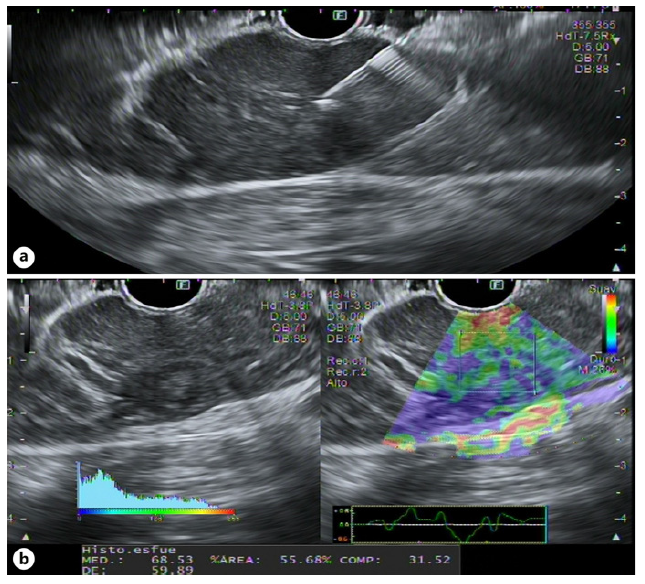

We present a 71-year-old female with no relevant past medical history. The patient was started on a proton pump inhibitor for dyspepsia, with complete symptomatic improvement. One year later, there was symptom recurrence with weight loss. Upper endoscopy revealed a 10 cm gastric subepithelial lesion, with central erosion (Fig. 1). Pathology evaluation was negative for malignancy. Computed tomography showed an extensive gastric wall lesion, with no adenopathies (Fig. 2). Endoscopic ultrasound (EUS) evaluation revealed an 8 cm subepithelial polycyclic hypoechoic lesion, with transition zone suggestive of the third/fourth layer origin (Fig. 3a). Quantitative elastography evaluation showed strain histogram 68 (Fig. 3b). The fine needle biopsy using a 22-G Franseen needle revealed clonal proliferation of plasma cells, positive for CD45/CD138 and negative for CD3/CD20/CD56 (Fig. 4). There was no anemia, hypercalcemia, or kidney impairment, and no abnormalities were found on bone marrow biopsy and myelogram apart from mildly increased plasma cell proliferation (5-10% of total cells). The positron emission tomography/computed tomography scan showed increased gastric uptake, with a maximum standardized uptake value of 3.3. Treatment consisted of surgical resection and the patient had an uneventful postoperative course. The surgical specimen confirmed the diagnosis.

Fig. 3 EUS showing an 8-cm subepithelial polycyclic hypoecoid lesion, with transition zone suggestive of the third/fourth layer origin (a). Quantitative elastography eval-uation showed strain histogram 68 (b).